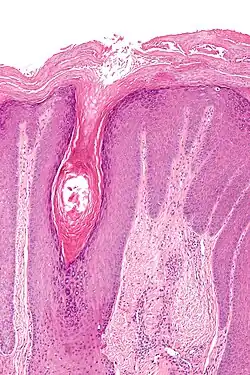

Die Diagnose erfolgt zum einen aus den Symptomen (Juckreiz, Lichenifikation und chronischer Verlauf), zum anderen aus der Histologie. Hierbei wird im Rahmen einer Biopsie eine Gewebeprobe aus dem veränderten Bereich entnommen und histologisch untersucht. Lichen simplex chronicus kann auf diese Weise sicher diagnostiziert werden. Im Vorfeld sollte an mögliche Differentialdiagnosen gedacht werden, z. B. allergisches Kontaktekzem, atopisches Ekzem oder Lichen ruber planus.